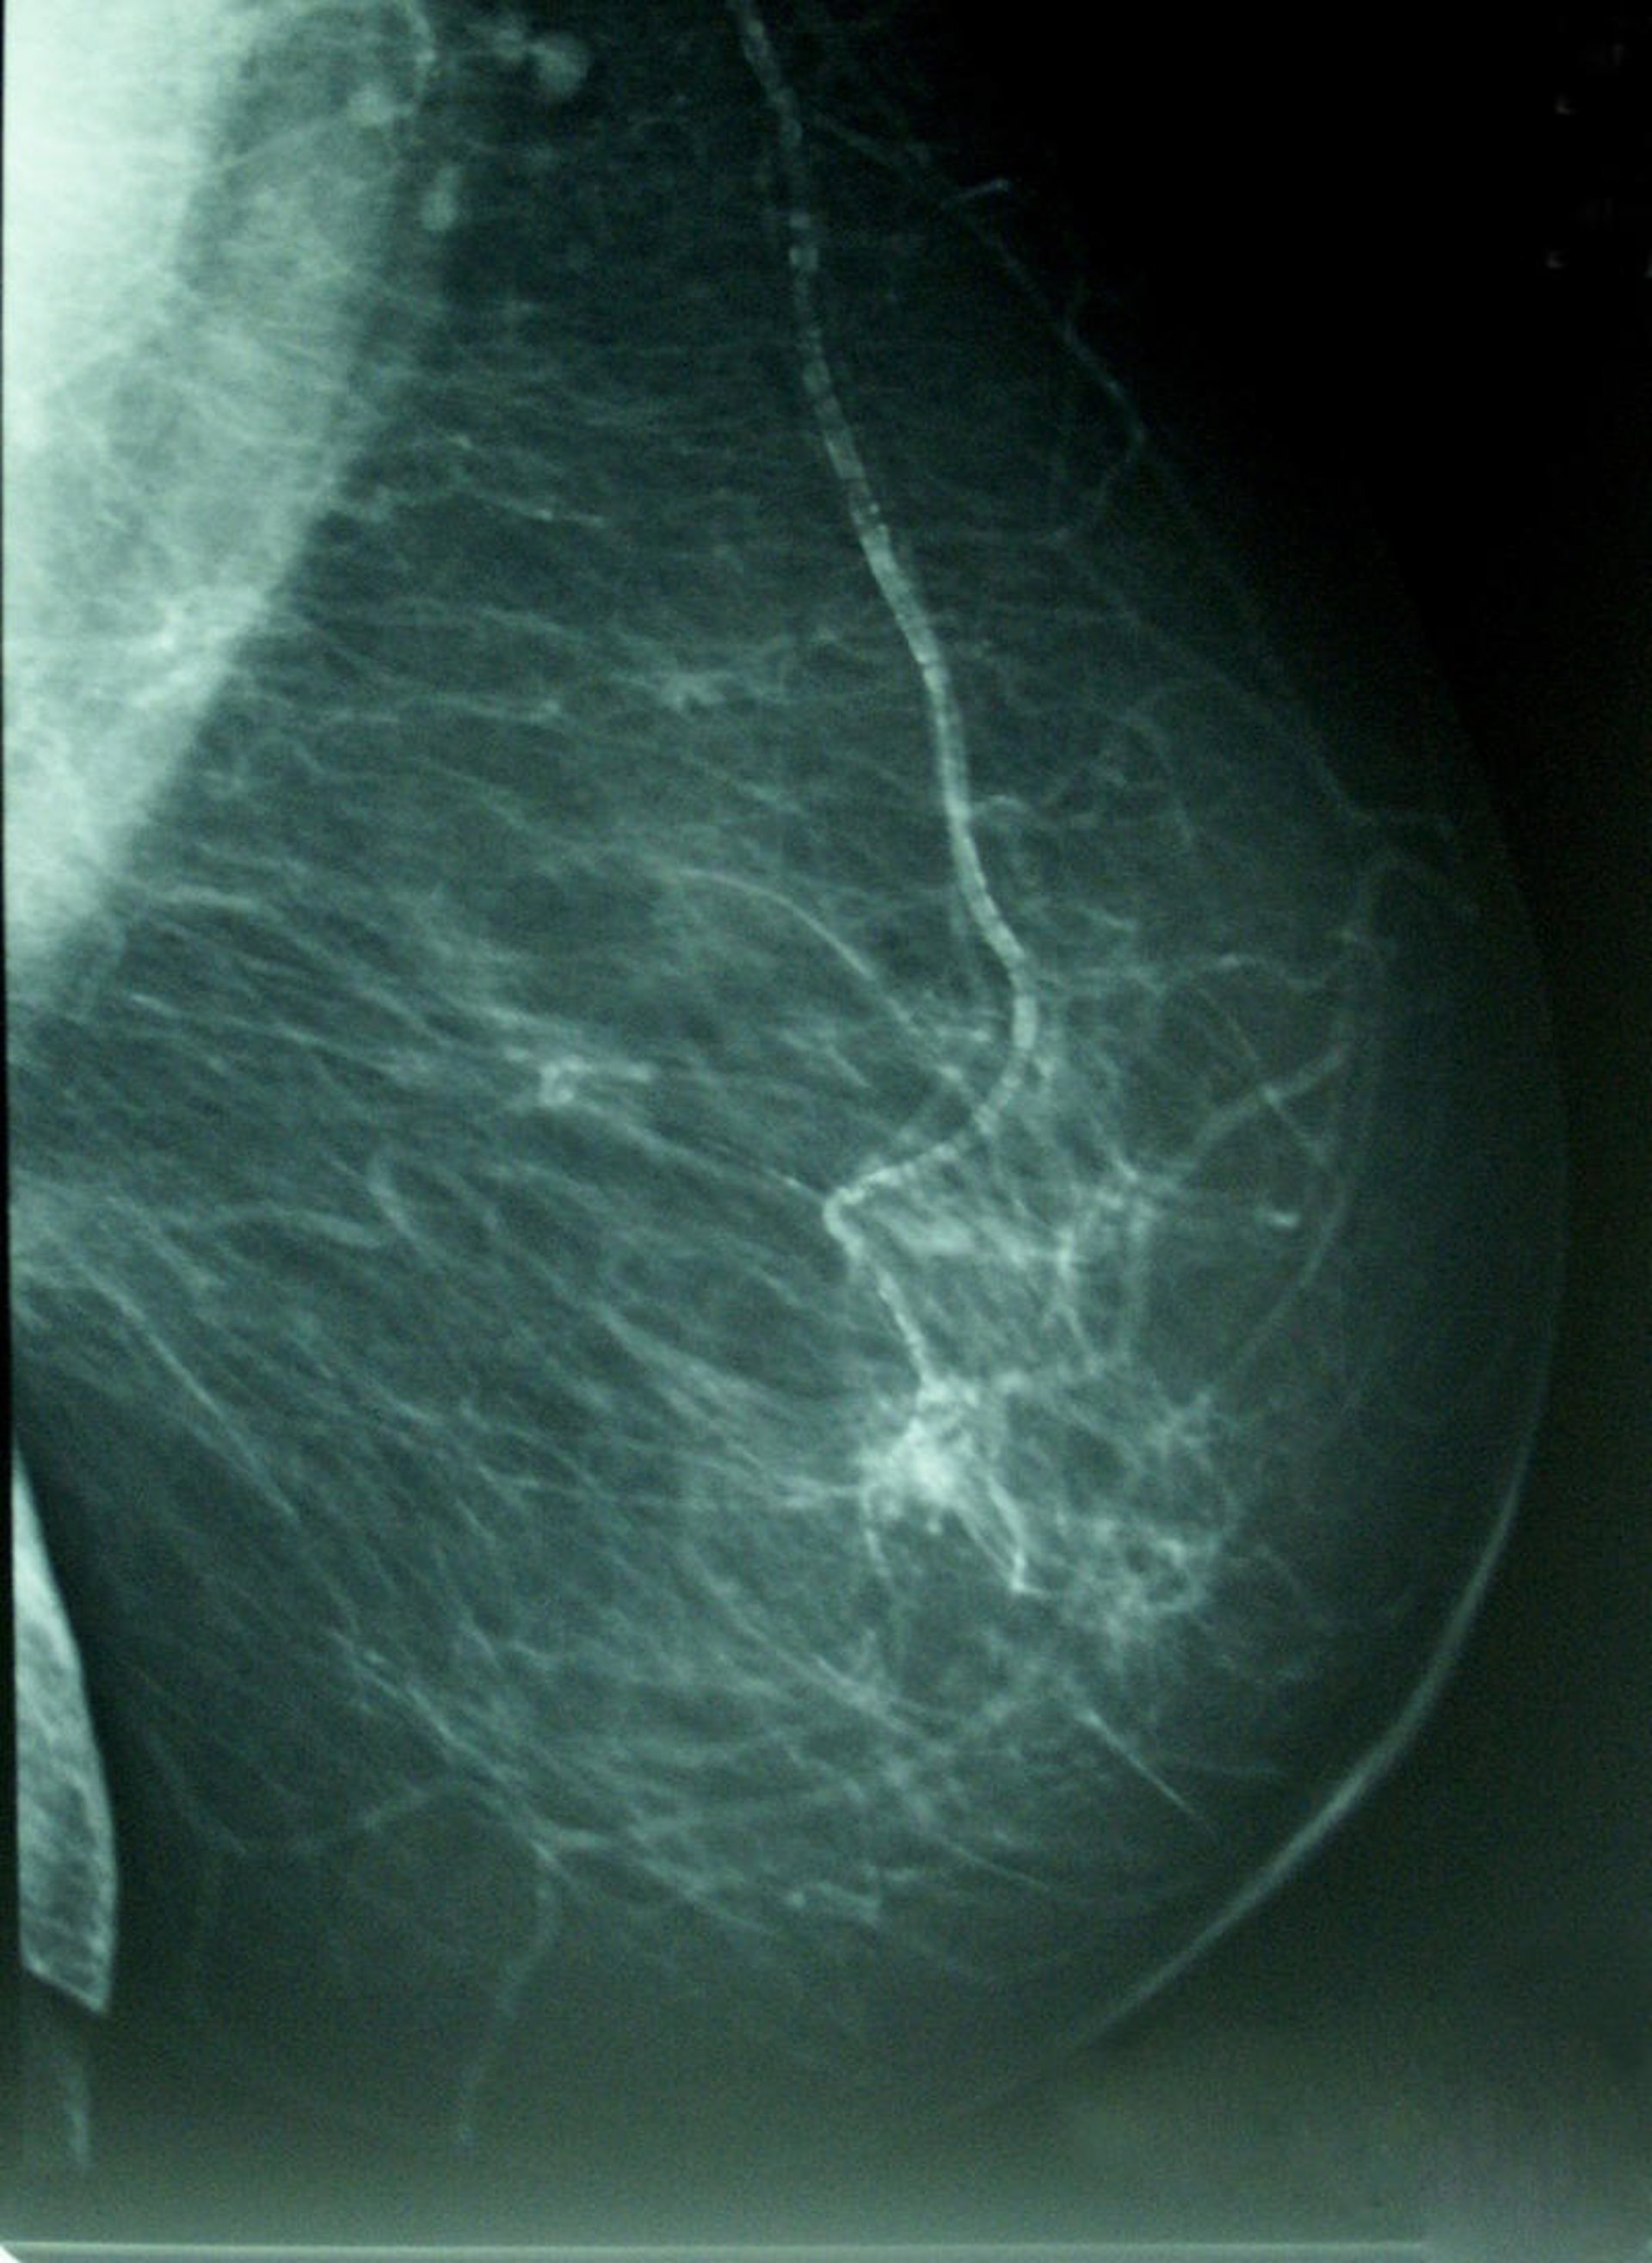

Cáncer De Mama, Densidad Mamográfica

Por eso, ha destacado las campañas de prevención y de diagnóstico precoz de la Región de Murcia y ha aconsejado a todas las mujeres comprendidas entre los 50 y 70 años que se hagan una mamografía.

En Murcia, gracias a dicha campaña de Prevención del Diagnóstico Precoz del Cáncer de Mama, hay unas 150.000 mujeres de entre 50 y 70 años que se hacen una mamografía cada dos años.

Es decir "que cada año la campaña tiene alrededor de 75.000 mujeres que se hacen una mamografía", ha explicado Navarrete, lo que ocurre es que no acude el 100 por cien, sino alrededor de un 75 por ciento, "por lo que se dejan de diagnosticar una cantidad significativa de cánceres por no acudir a realizarse la prueba".

Tras lo que ha hecho un llamamiento para que todas las mujeres de esas edades se hagan una mamografía porque el diagnóstico precoz "consigue que el tumor se detecte antes de que se palpe", es "la mejor manera de poder luchar contra esta enfermedad" y tiene mucha posibilidad de curación. Además, ha apostillado, en los últimos bienios, se han diagnosticado más de 235 casos en la campaña de prevención.